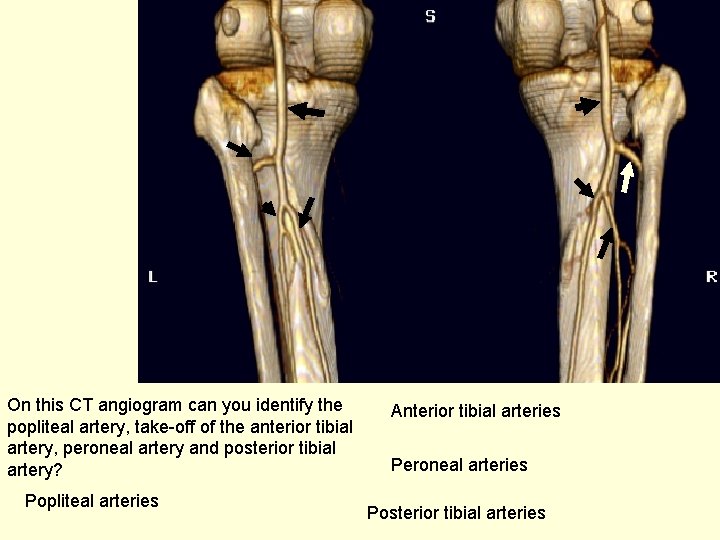

On this CT angiogram can you identify the popliteal artery, take-off of the anterior tibial artery, peroneal artery and posterior tibial artery? Popliteal arteries Anterior tibial arteries Peroneal arteries Posterior tibial arteries

This is a patient with complete disruption of the distal superficial femoral artery/upper popliteal artery. You can see how it is reconsitiuted (through collaterals) at the level of the knee joint. Disrupted Reconstituted